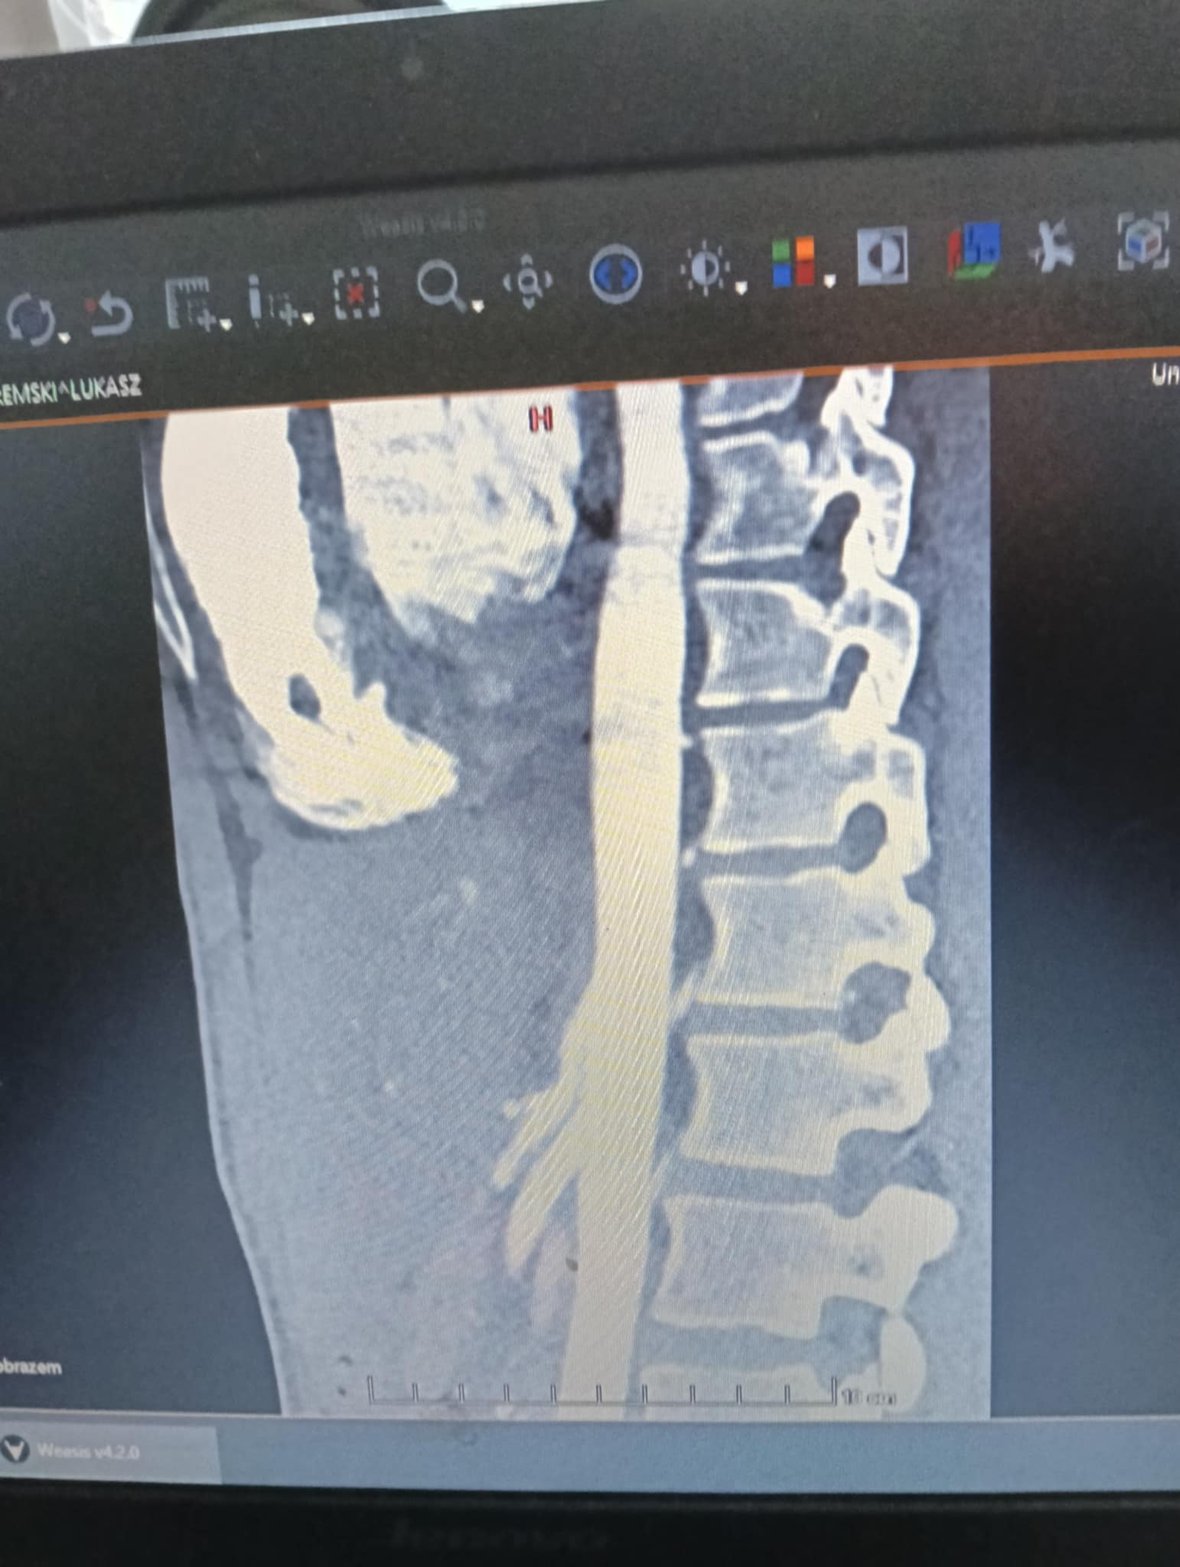

Kochani 4 lipca W Warszawie Pani Kardiolog potwierdziła u Łukasza zespół MALS. Mogło już być potwierdzone w lutym ale niestety trzeba było wyjechać do stolicy by otrzymać Ostateczna diagnozę po 2,5 roku batali od lekarza do lekarza,setki badań nie potrzebnych, ogromnego cierpienia i ogromu błędów. Radość ogromna. Jest nadzieja. Czekamy obecnie na wytyczne od Lekarza chirurga naczyniowego. Czekamy na decyzję odnośnie operacji. Operacja ma dać nam drugie życie, ma skończyć się cierpienie. Jeszcze kilka wyjazdów do Warszawy. Kochani każda złotówka przybliża nas do zdrowia.